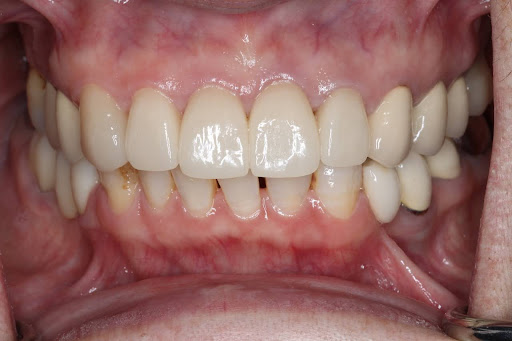

削らず、美しく整える “矯正 × セラミック治療” の治療選択肢

「歯をあまり削りたくない」「でも見た目も整えたい」そんな方のために、矯正とセラミック治療を組み合わせた方法です。先に歯並びを整えることで、必要以上に削らず、自然でキレイな見た目に仕上げることができます。噛み合わせも良くなるため、治療も長持ちしやすいのが特徴です。

このような方に、当院の矯正×セラミック治療のハイブリッド治療は特におすすめです。